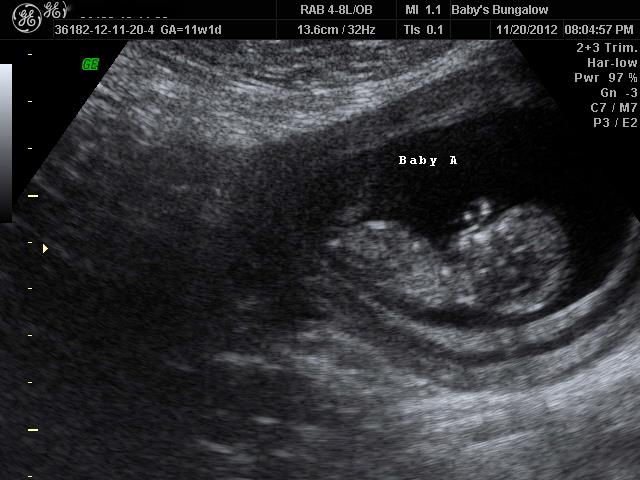

I had an elective u/s tonight at 11w1d. We didn't even expect the tech to guess, as we were only going so that we could get some clear shots of the babies to bring to Thanksgiving on Thursday. No one knows we're pregnant yet, let alone having twins, except for our parents.

Anyway, the tech was great and got lots of good shots of the babies, even some in 3D, which we weren't expecting. Then the owner of the place came in, and they both were examining the shots and talking to each other about how it seems like they could give a good guess on the babies' genders. They said it would be just a guess, as it was so early, but they were pretty sure that Baby A was a girl, and that Baby B was a boy. In fact, they said they'd be shocked if Baby B was anything but a boy - they said he had a very clear boy nub.

I was totally okay with thinking I'd get one of each, even though I'd love two girls. But then things took a turn for the worse, and suddenly, they weren't sure about Baby A being a girl anymore. They said the nub looked flat in some shots, then slightly angled in others. They looked and looked, and then finally decided that they really couldn't tell with Baby A, but were pretty sure Baby B was a boy.

Here are some shots of the babies....

Baby A

Attachment 6509

What do you think? Can you even see any nubs in these pictures? It was a lot clearer during the ultrasound session, maybe I should have bought the CD. I have another question too - once a nub is rising, or if it's "slightly raised," there's no chance of it going down, right? I mean, at this stage, all nubs are pretty flat, and then rise if they're boys, right? I admit I'm not great at the nub theory, and I do realize it's very, very early to even be obsessing about this....but I feel like all my hope for ever having a girl has just been totally squashed.